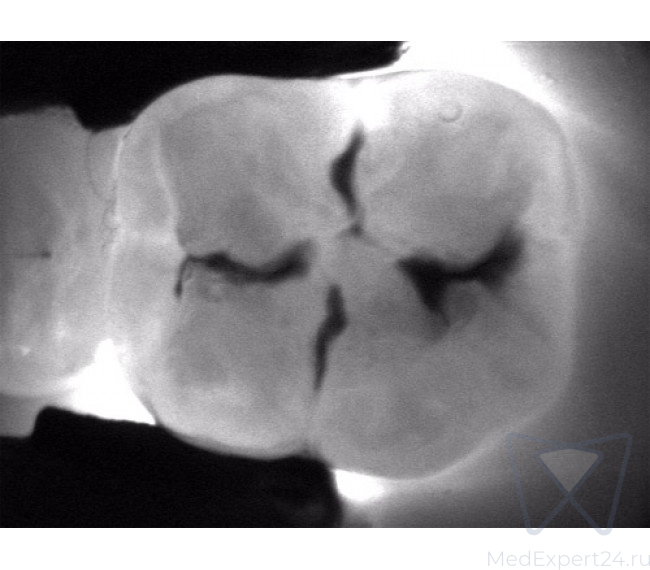

KaVo DIAGNOcam дает Вам полную уверенность в точности результата диагностики. С его помощью Вы сможете обнаружить кариозные поражения на самом раннем этапе развития.

KaVo DIAGNOcam позволяет визуализировать их на аппроксимальных и окклюзионных поверхностях зубов и обеспечивает проведение диагностики вторичного кариеса (при небольшом размере пломбы).